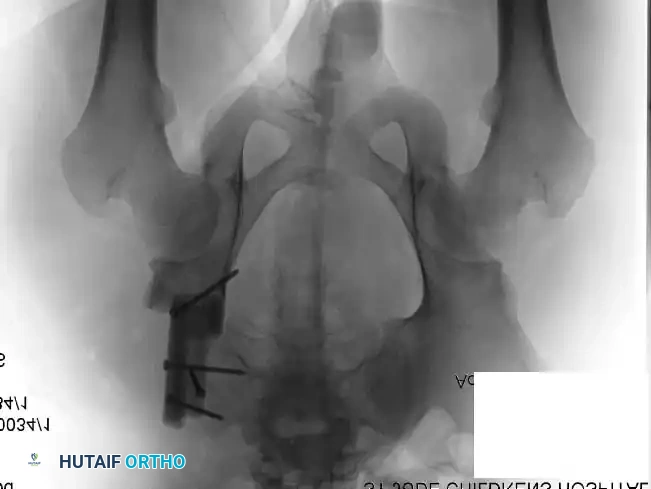

Intraoperative Imaging and Margin Assessment

Continuous intraoperative assessment using fluoroscopy and frozen section pathology is mandatory. The following images demonstrate various stages of complex upper extremity resections, allograft preparations, and prosthetic implantations across the humerus and elbow joint.